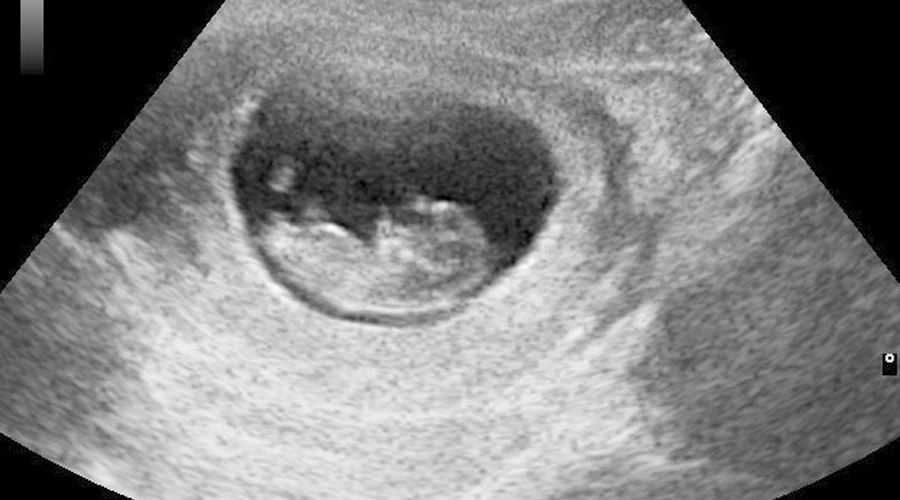

La ley de “Justicia e Igualdad para infantes vivos” LIFE (Vida, por sus siglas en inglés) limita el aborto hasta las primeras seis semanas de gestación. Actualmente el aborto es legal en Georgia hasta la semana 20.